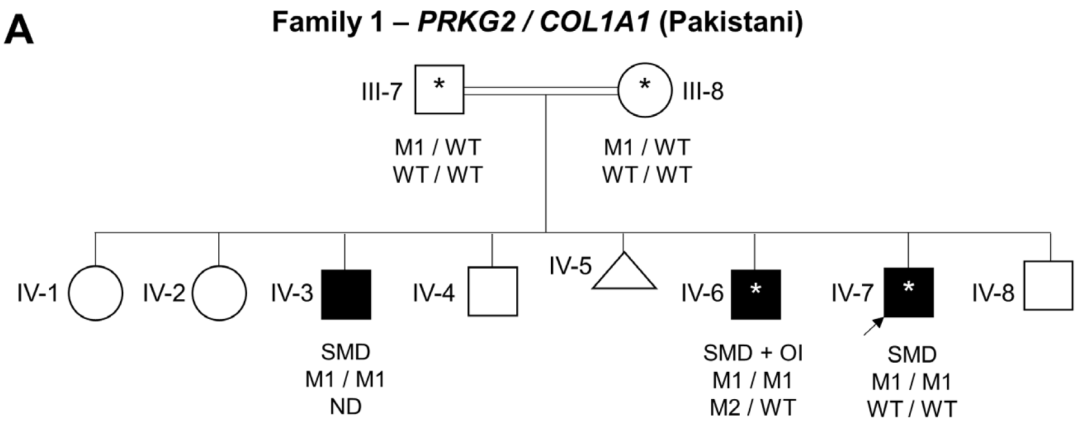

在家族1中,通过WGS和Sanger测序在3个患有椎体-骺端发育不良 (Spondylometaphyseal dysplasia, SMD)的兄弟中发现了一个纯合子致病突变PRKG2 (NM_006259.3:c.2282dup, p.Asp761Glufs*34)。有趣的是,F1-IV-6患者 (中度致病)也有I型成骨不全 (Type I osteogenesis imperfect, OI)。一项早期临床外显子组测序研究发现,在分子诊断的病例中,有4.6%的病例有一个以上的基因变异导致混杂 (Blended)表型。

家系1家系分析图(双线为近亲婚配),箭头先证者M1/M1突变

这样的复杂病例预计在近亲的家庭中更为常见,大范围纯合子区域 (ROHs)占基因组的很大比例;然而,对于F1-IV-6,OI的二次诊断是由于COL1A1移码引起的,这是从头开始出现的。这名儿童因儿童时期多发骨折 (婴儿时手臂、8岁手腕和胸部T6楔形骨折)伴有蓝色巩膜而怀疑患有OI。当然,同时存在的OI可能对这个个体的表型严重程度有影响,尤其是因为他的身高比他的两个兄弟更低,OI (1型)是一种已知的导致身材矮小的原因。

在家系2中,一个患有肢端发育不良的女孩的外显子组测序显示了一个纯合子致病变异PRKG2c.1705C>T;(Arg569*)。将F2-V-3的基因组数据与之前发表的病例进行比较,未能检测到PRKG2基因座 (Locus)上共有的单倍型。c.1705 C>T的复发似乎更有可能是由于单独的突变事件。

家系2家系分析图,女孩M3/M3突变